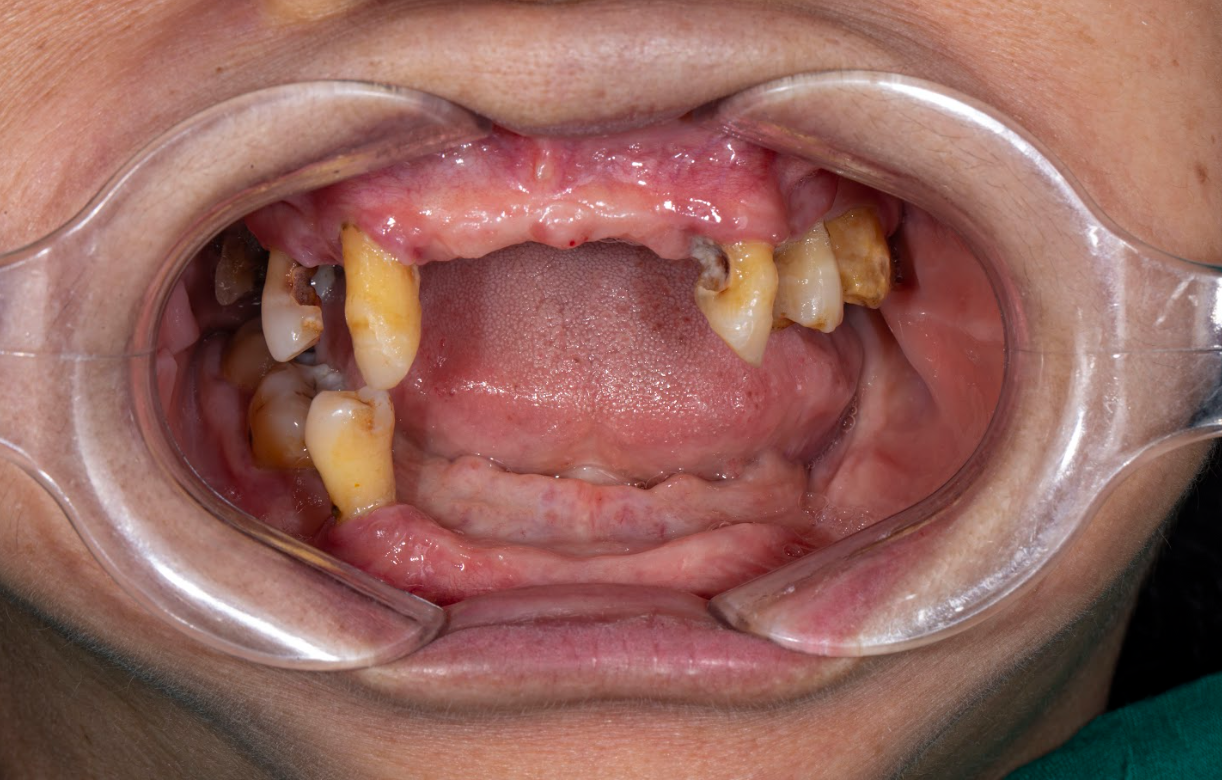

Tình trạng gì xảy ra khi mất răng lâu năm?

Mất răng không chỉ ảnh hưởng đến thẩm mỹ mà còn dẫn đến hàng loạt hậu quả nghiêm trọng nếu để lâu năm. Cụ thể:

- Tiêu xương hàm: Khi răng mất đi, xương ổ răng không còn được kích thích và sẽ dần tiêu biến.

- Lệch khớp cắn: Các răng bên cạnh có xu hướng nghiêng vào khoảng trống, làm sai lệch khớp cắn.

- Gương mặt già hơn: Mất răng lâu ngày khiến vùng má hóp, da chùng nhão, khuôn mặt biến dạng.

- Ảnh hưởng tiêu hóa: Ăn nhai khó khăn dẫn đến tiêu hóa kém, ảnh hưởng đến sức khỏe toàn thân.

Mất răng lâu năm có trồng Implant được không?

Câu trả lời là CÓ, nhưng cần đánh giá kỹ lưỡng tình trạng xương hàm, mô mềm, và sức khỏe tổng quát trước khi quyết định cấy ghép Implant. Với sự hỗ trợ của công nghệ hiện đại, thậm chí những ca mất răng >10 năm vẫn có thể điều trị thành công.